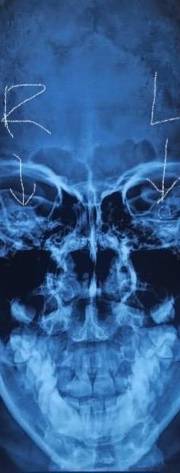

Capturing the essence of this achievement, our hashtags #bilateralcochlear, #simultaneouscochlear, and #adultbilateralcochlearimplants underscore our commitment to advancing medical frontiers. The accompanying X-ray showcases the electrode array, a visual testament to both our technical prowess and the promise of a harmonious future for the patient.